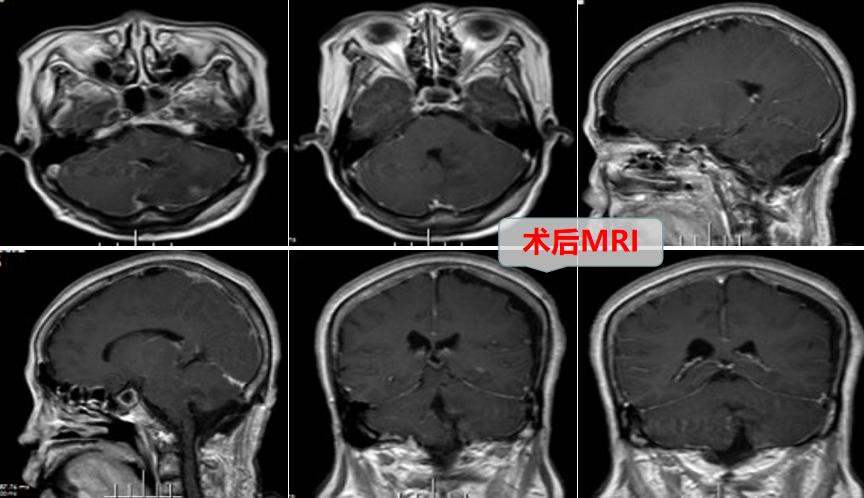

术中可见肿瘤质韧,边界清晰,位于左侧小脑半球至小脑蚓部达四脑室。神经外十科团队在高清显微镜下,精准仔细操作,顺利全切肿瘤。术后病理确诊脑膜瘤。欧阳辉教授解析,考虑为四脑室出口处脉络丛或蛛网膜起源的良性脑膜瘤,生长突入四脑室并挤压左侧小脑半球,此种情况的脑膜瘤临床较少见。

术后,陈阿姨很快恢复意识,肢体活动良好,走路也没有再歪向一侧,已于日前顺利出院。